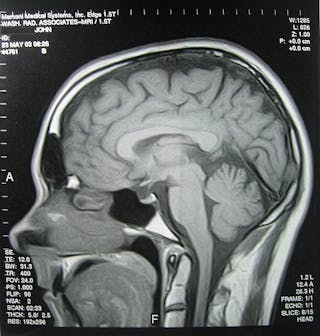

Eventi globali come il cambiamento climatico e un commercio internazionale hanno causato l’emergere di una serie di parassiti pericolosi in paesi in cui non sono stati trovati prima. I parassiti, che possono invadere e danneggiare gli organi vitali del corpo come il cervello, vanno da organismi unicellulari a vermi a nastro relativamente grandi. Qui ci sono cinque che, anche se ancora per fortuna rara, hanno fatto la sua comparsa in luoghi nuovi.

L’infezione umana è rara e colpisce solo quelli con sistema immunitario compromesso (per esempio cancro o pazienti HIV/AIDS), ma il risultato è sempre fatale meningo-encefalomielite – un’infiammazione del cervello, del midollo spinale e delle loro membrane. Questa è stata la causa della tragica morte di due pazienti che hanno ricevuto reni infetti nel novembre 2014 in Galles.

A volte le larve attraversano la barriera emato-encefalica ed entrano nel sistema nervoso centrale (SNC), dove gli embrioni si sviluppano in cisti piene di liquido che portano a una condizione nota come neurocysticercosis che si traduce in convulsioni ed è una delle infezioni parassitarie più pericolose del SNC in tutto il mondo. La diagnosi di neurocysticercosis è difficile a causa della mancanza di sintomi clinici specifici. La malattia – che normalmente colpisce persone in Sud America, Asia e Africa sub-sahariana – è stata eccezionalmente rara nei paesi occidentali, tuttavia alcuni casi sono stati segnalati nel Regno Unito e negli Stati Uniti.

Naegleria fowleri – comunemente nota come ameba che mangia il cervello-è unicellulare e vive liberamente e prospera in corpi d’acqua caldi. Questo parassita può causare una rara infezione cerebrale chiamata meningoencefalite, che causa una grave infiammazione cerebrale. L’ameba causa anche tutta una serie di altri sintomi neurologici e ha un tasso di mortalità che si avvicina al 100%.

Se l’acqua contenente l’ameba entra nel naso, il parassita può viaggiare attraverso i nervi olfattivi, che sono responsabili della rilevazione delle molecole odorose e della loro trasmissione come segnali al cervello. I sintomi iniziali compaiono in meno di una settimana dopo l’infezione e comprendono febbre, mal di testa, nausea, rigidità al collo e vomito. Man mano che l’infezione progredisce, i pazienti sviluppano mancanza di attenzione, perdita di equilibrio, convulsioni, allucinazioni e infine coma e morte.

L’infezione si acquisisce bevendo acqua contenente crostacei infetti, ingerendo rettili o rane infette crude o utilizzando un impiastro di rana cruda per curare gli occhi irritati. Le infezioni da Spirometro sono caratterizzate dalla comparsa di grandi noduli al di sotto della pelle e dal gonfiore dei muscoli che controllano il movimento oculare. L’infezione può anche coinvolgere il cervello e il midollo spinale. La diagnosi di infezione si ottiene mediante biopsia della lesione, imaging e metodi diagnostici.